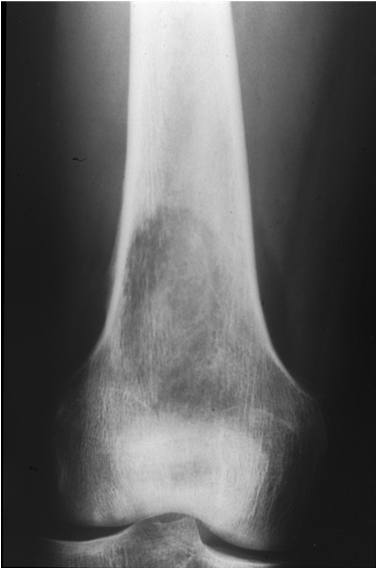

Fig. 18. An osteosarcoma is seen as an ill-defined lesion with a permeative pattern of bone destruction with cortex involvement in the distal metaphysis of the femur.

Most expansile, lucent lesions are located in the medullary space of the bone. A good way to further describe a lesion is noting its relationship to the physis. Many lesions have predisposition in specific parts of the bone, which reflects their “original tissue”. For example, a chondroblastoma will arise in the epiphysis whereas an osteosarcoma usually originates from the metaphysis. Round cell lesions like Ewing’s sarcoma are typically seen in the diaphysis.